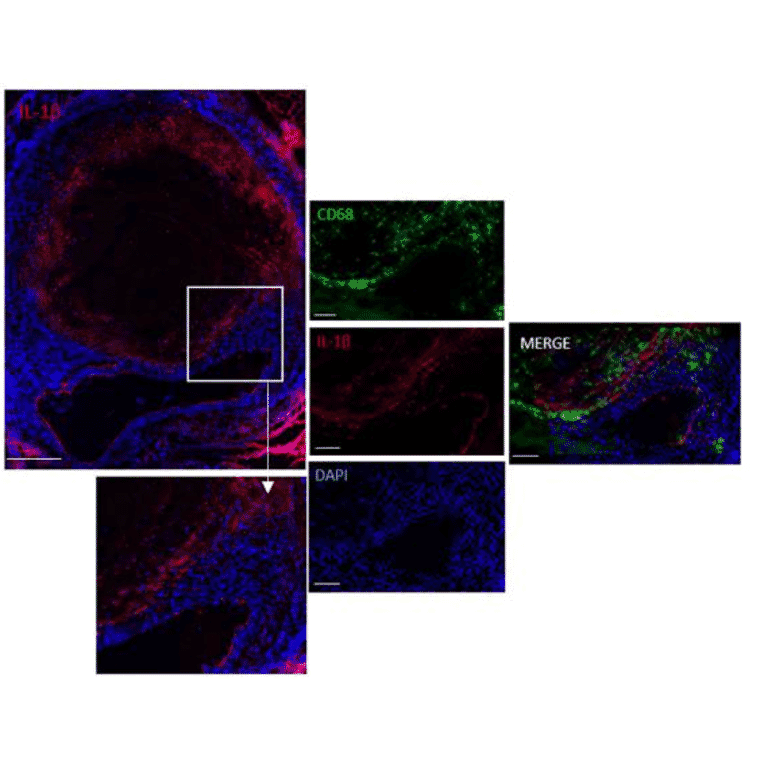

Results: Mice of the Ang-II+01BSUR-group showed a lower aortic-diameter compared to mice of the Ang-II-group and control mice (p < 0.05). Using the elastin-specific-probe, a significant decrease in elastin-destruction was observed in mice of the Ang-II+01BSUR-group. In vivo MR-measurements correlated well with histopathology (y = 0.34x-13.81, R2 = 0.84, p < 0.05), ICP-MS (y = 0.02x+2.39; R2 = 0.81, p < 0.05) and LA-ICP-MS. Immunofluorescence and western-blotting confirmed a reduced IL-1ß-expression.